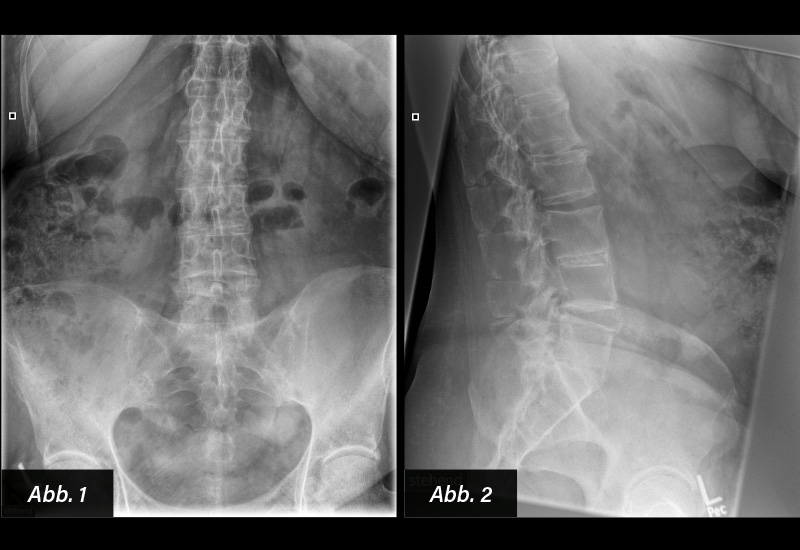

BILDGEBENDE DIAGNOSTIK:

Röntgen (s. u.)

DIAGNOSE: Bandscheibenverkalkung und langjährige Spondylitis ankylosans

Meist handelt es sich um radiologische Zufallsbefunde. Im Erwachsenenalter bedingt die Bandscheibenverkalkung meist keine klinische Symptomatik. Bandscheibenverkalkungen werden mit zunehmendem Lebensalter auch in Assoziation bzw. Kombination mit meist degenerativen Wirbelsäulen-und Bandscheibenveränderungen beobachtet. Auch im Zusammenhang mit entzündlichen Wirbelsäulenerkrankungen, z. B. einer langjährigen Spondylitis ankylosans, können Bandscheibenverkalkungen beobachtet werden.

BEWERTUNG: Die Bandscheibenverkalkung wird im zunehmenden Erwachsenenalter häufiger bei der Röntgendiagnostik, vor allem der Lendenwirbelsäule, als Zufallsbefund beobachtet. Die möglicherweise assoziierte Rückenschmerzsymptomatik beruht meist auf degenerativen oder entzündlichen Wirbelsäulenveränderungen und nicht auf der Bandscheibenverkalkung.